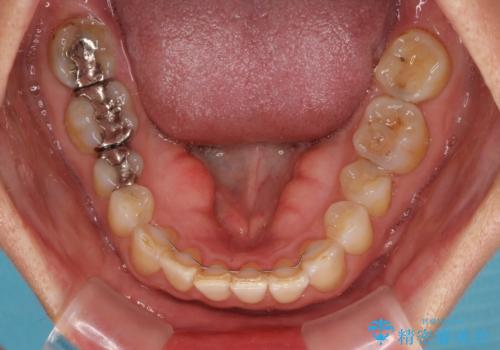

- 前歯のデコボコと上下正中のずれを気にして来院された患者様です。

下顎骨が骨格的にずれがあったため、しっかりと正中を合わせるとなるとワイヤー矯正が必要でしたが、マウスピース矯正を希望されたため、極力正中を合わせることを目標に、インビザラインにて矯正治療を行うこととしました。